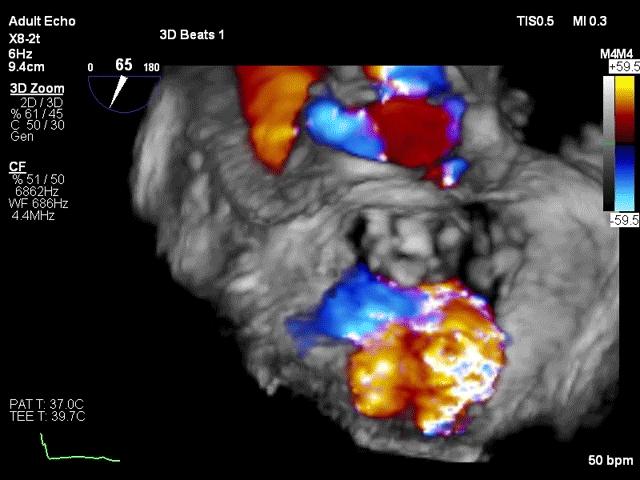

术前超声评估

该例患者为57岁男性,因扩张型心肌病合并严重心功能不全,并伴有高尿酸血症、高脂血症等疾病。超声心动图评估提示二尖瓣重度反流、轻微主动脉瓣反流与轻微三尖瓣反流,LVEDD 83mm,LVESD 73mm,LVEF 34%。二尖瓣反流机制为功能性反流,有效反流口面积为0.49cm²,反流量93mL,瓣口面积为6.7cm²。